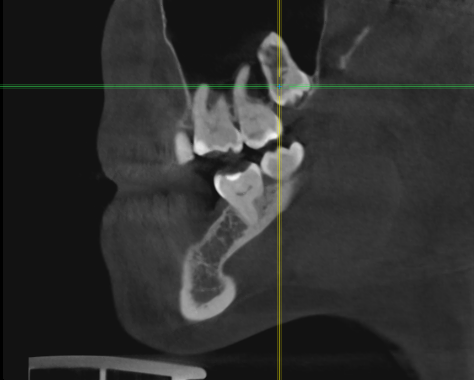

Женька Опубликовано 1 апреля, 2021 Поделиться Опубликовано 1 апреля, 2021 Значит придётся пациентке отказать... Не понимаю пока куда тут можно зслить и как. Про бш помню-знаю. Но топить нужно же не в кости 3-4 мм? Ссылка на комментарий

Женька Опубликовано 6 апреля, 2021 Поделиться Опубликовано 6 апреля, 2021 01.04.2021 в 22:47, annda сказал: Тишью левел еще есть так- то, это если про биологическую ширину речь вести и не топить и припилить кость. Но ЗСЛ нужен в любом случае, либо бикортикальная фиксация( на 1-2 мм без графта приподнять). А между зубами для коронки места достаточно? тот что на срезе это 7мм с 1.5мм полированной шейки, я же правильно понимаю, что это подобие тишью левел и с ним можно также обращаться? Да, между зубами премоляр проходит. Ссылка на комментарий

Женька Опубликовано 1 мая, 2021 Поделиться Опубликовано 1 мая, 2021 01.04.2021 в 13:26, red_butler сказал: заглубить с проведением ЗСЛ у все пройдет Ну что же. Пациентка согласилась на синус и имплантацию...а я надеялся что нет Только планирую пойти через открытый все-таки. Тк во-первых это можно сказать первый синус, во-вторых боюсь что при зсл я получу перфо ввиду анатомии синуса. Ссылка на комментарий

Irouil Опубликовано 1 мая, 2021 Поделиться Опубликовано 1 мая, 2021 (изменено) Вы тут с открытым синусом в 10 раз вероятнее накосячите, чем с закрытым Потому что даже если просто перфорнуть тут пазуху при ЗСЛ с очень высокой долей вероятности произойдёт чуть менее чем ничего А если начать отслаивать слизистую пазухи отдельным доступом, да еще и прямо по медиальной границе альвеолярной бухты, да еще и так высоко, да еще и планировать натолкать туда графта или еще какой-нибудь дряни... сразу ЛОРа хорошего номер ищите) Изменено 1 мая, 2021 пользователем Irouil 2 1 Ссылка на комментарий

Женька Опубликовано 2 мая, 2021 Поделиться Опубликовано 2 мая, 2021 А я думал наоборот. Открытый проще во всех смыслах Предлагаете просто зсл, губку если перфо внутрь, если нет то просто поднять пазуху и всё? без графтов чисто на сгустке? Ссылка на комментарий

Irouil Опубликовано 2 мая, 2021 Поделиться Опубликовано 2 мая, 2021 Без графтов, преп на -1-1.5 мм от высоты гребня пилотном, потом конденсация до 3.2 (или какой там у Вас диаметр вогнутого остеотома), дальше стук, по необходимости конденсинг и профайлинг крестального модуля либо реверс-препинг всей длины (в зависимости от планируемого винта) потом просто крутить 8 мм в этой ситуации на мой взгляд ничем графтить не нужно Ссылка на комментарий